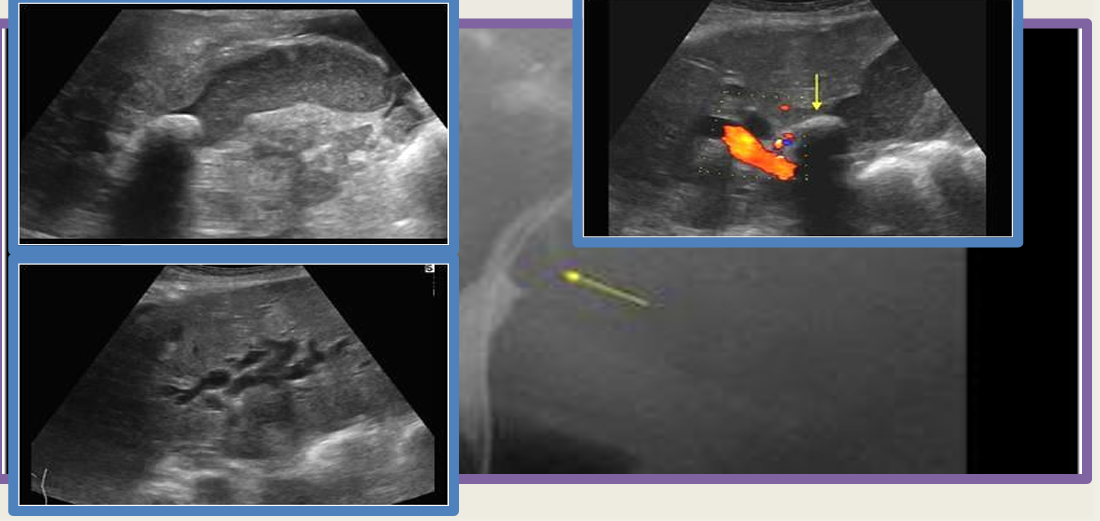

strawberry GB

mucocele

cholecystitis

gangrenous GB